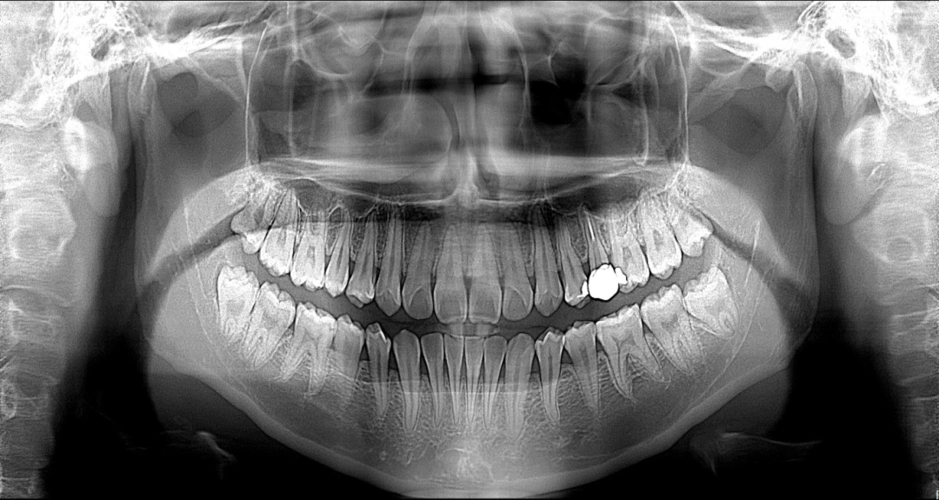

口腔x光扫描全景图